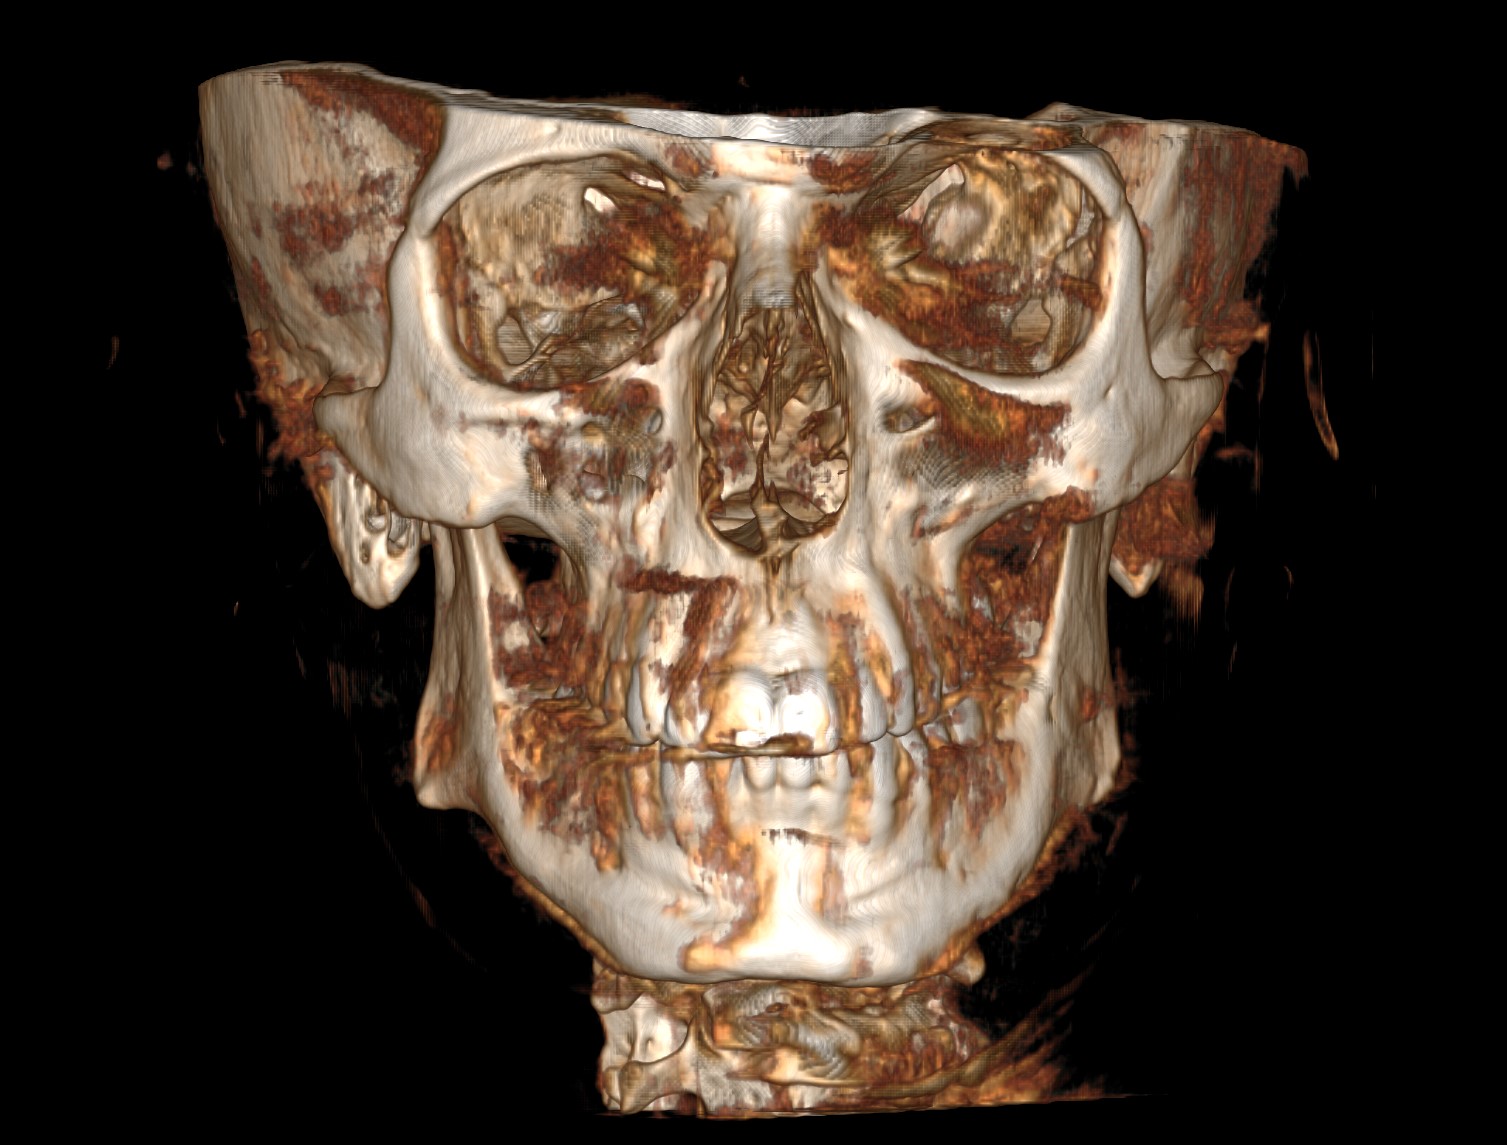

CBCT (Front + Side) + OPG (Old Before & New After braces) (need decompensation)

My Analysis (Based on CBCT):

- Gonial Angle: 131.8°

- Inter-molar Width: ~34.7mm (Narrow palate, teeth in compensation).

- Face Type: High divergence, nasolabial folds, poor midface & infraorbital support)

- Bimax (BSSO + Lefort 1) with CCW Rotation: I need to close that 132° angle and get projection.

- Skeletal Expansion (MARPE/MSE/FME/SARPE): My inter-molar width is ~34.7mm. I’m debating and honestly I don't have much knowledge about this. I want to maximize midface widening and cheekbone support. Given I'm planning Bimax anyway, which one would you guys suggest?

- Midface support: I’m leaning towards custom PEEK inframalar/infraorbital implants but I want to know if I can avoid paranasal implants by performing a High LeFort I cut and advancing the ANS, or maybe eventually both?

- Jaw/Angles: I definitely lack bone mass here too. I'm considering custom jaw implants (wraparound or angles), but I’m worried about two things: 1) Is it even possible to do Bimax + Midface + Jaw implants in a single op? 2) The budget might explode.

- Genioplasty: Undecided. If the CCW rotation provides enough projection, I might skip it, but idk tbh.